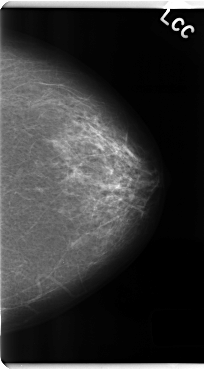

C_0182_1.LEFT_CC

LEFT_CC LINES 4792 PIXELS_PER_LINE 2648 BITS_PER_PIXEL 12 RESOLUTION 50 NON_OVERLAY